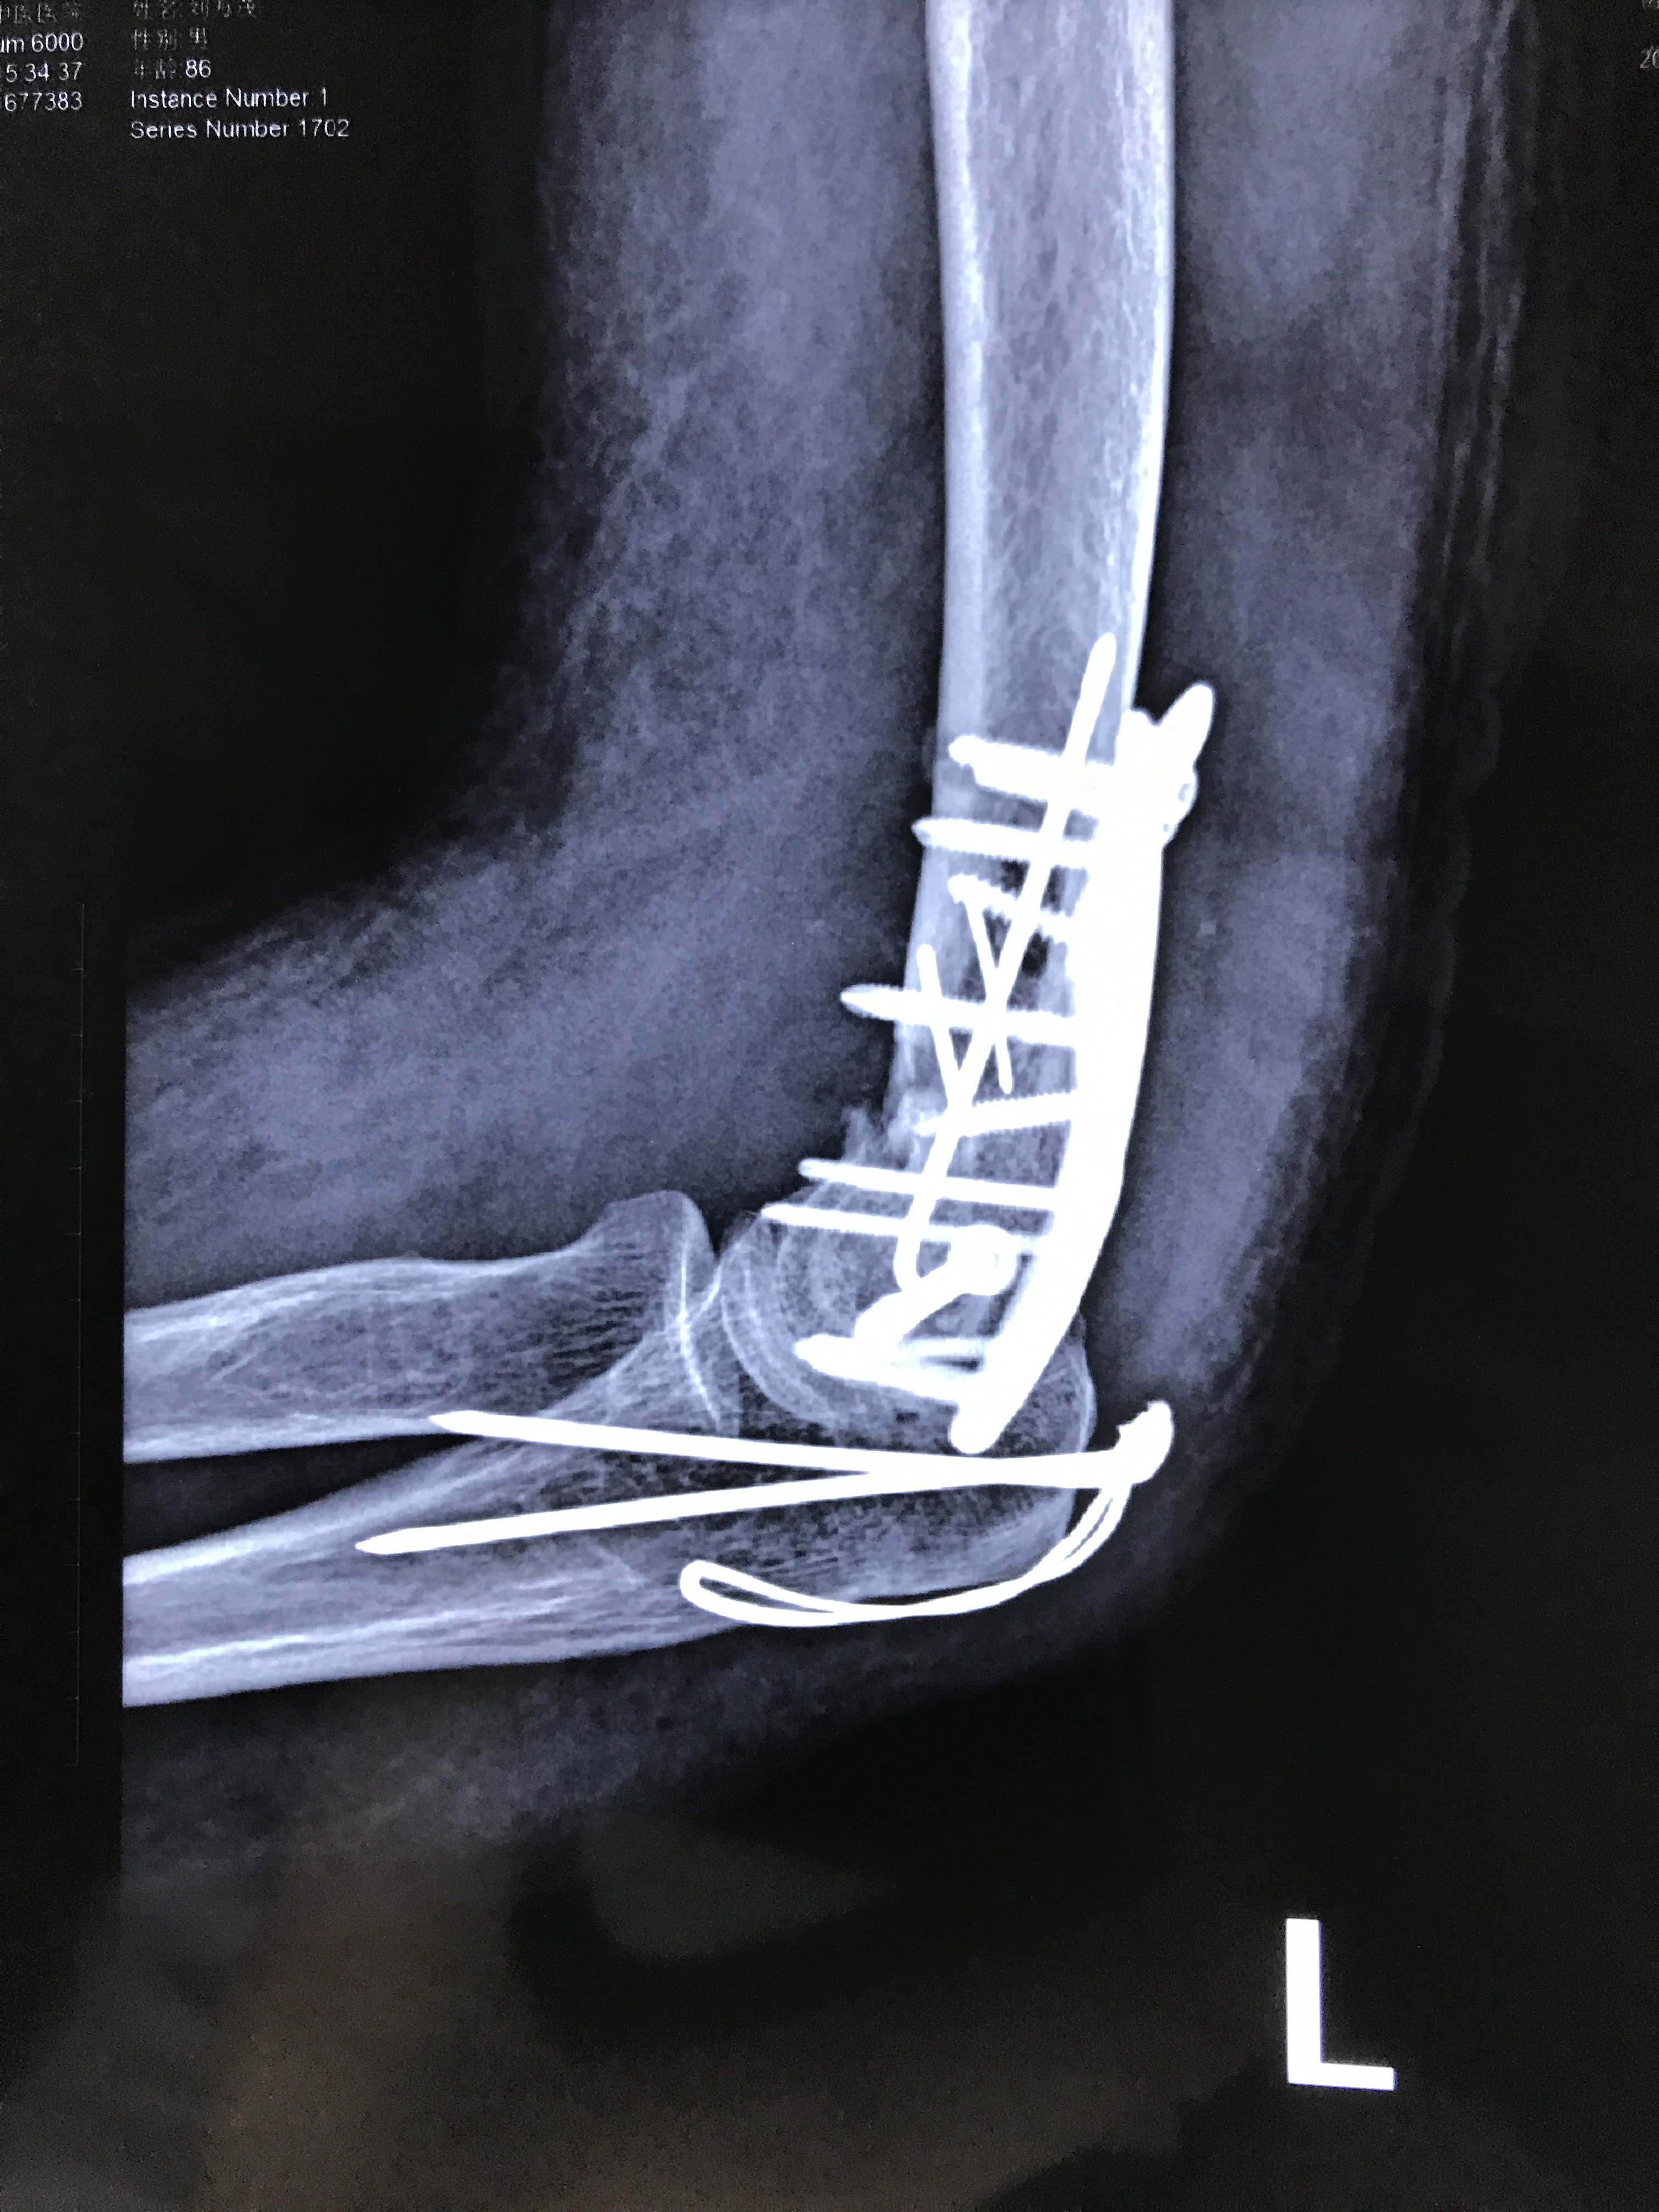

老年肱骨髁间粉碎性骨折 (原创)

辅助检查:x线,ct 临床诊断:左肱骨髁间骨折(iii型) 治疗经过:外院转